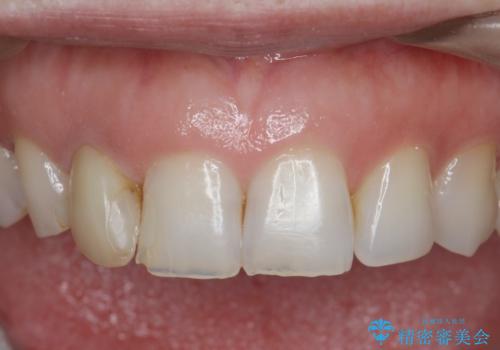

- 前歯の付近、歯ぐきを押すと違和感を感じその改善を求めて来院されました。

X線検査の結果、失活(感染根管)であることが判明したので、感染根管治療後セラミック補綴を計画します。